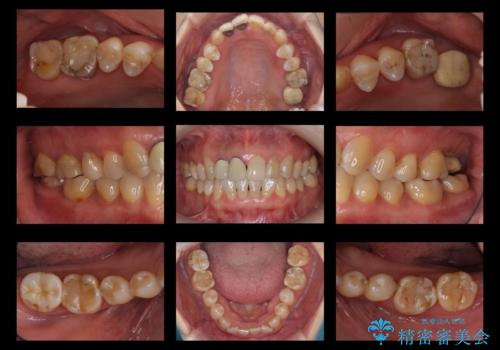

全体的な虫歯治療 他院で入れたインプラントの続きも

- 前歯のかぶせ物のやりかえと、全体的な治療をご希望して来院。

左上は他院でインプラントを入れたが、クラウンの脱離を繰り返して、仮歯に戻したあともうそれでいいと言われたとのことでした。

仮歯はすっかり劣化、変質しており、上記の写真のように隣の歯が虫歯になっている状態でした。

全体的にプラスチックで治療してあり、劣化していたのと、また、右上6番は根の治療がされていましたがプラスチックで埋めてあるだけで中を見たところ残念ながら割れていました。その歯は抜歯し⑤6⑦ブリッジにしています。

全体的にしっかり治療を行い、メンテナンスにはいることができました。